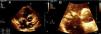

Se realizó un ecocardiograma transtorácico (ETT) (figs. 1 y 2), donde se apreció una imagen ecogénica en la valva anterior de la tricúspide, compatible con vegetación mayor de 17×21mm que generaba déficit en la coaptación valvular con insuficiencia de la misma, además de una disfunción sistólica del ventrículo derecho con un TAPSE de 8mm y un ventrículo derecho de 41mm en su base, con desplazamiento del tabique interventricular hacia la izquierda. Aurícula derecha dilatada, con desplazamiento del septum interauricular hacia la izquierda. Flujo pulmonar con un tiempo de aceleración de 95ms y una presión media de la arteria pulmonar de 32mmHg. Se confirmaron hallazgos a través de ecocardiograma transesofágico (ETE), realizado sin complicaciones.

Ecocardiograma transtorácico. Plano paraesternal eje corto o transversal a nivel de los grandes vasos. A) Aurícula derecha (AD), aurícula izquierda (AI), ventrículo derecho (VD), válvula aórtica (Ao), imagen ecogénica en la valva anterior de la tricúspide, compatible con vegetación mayor de 17×21mm). B) Ampliación del aparato valvular tricúspide donde se observan imágenes ecogénicas en ambas valvas, siendo la mayor la observada en valva anterior.